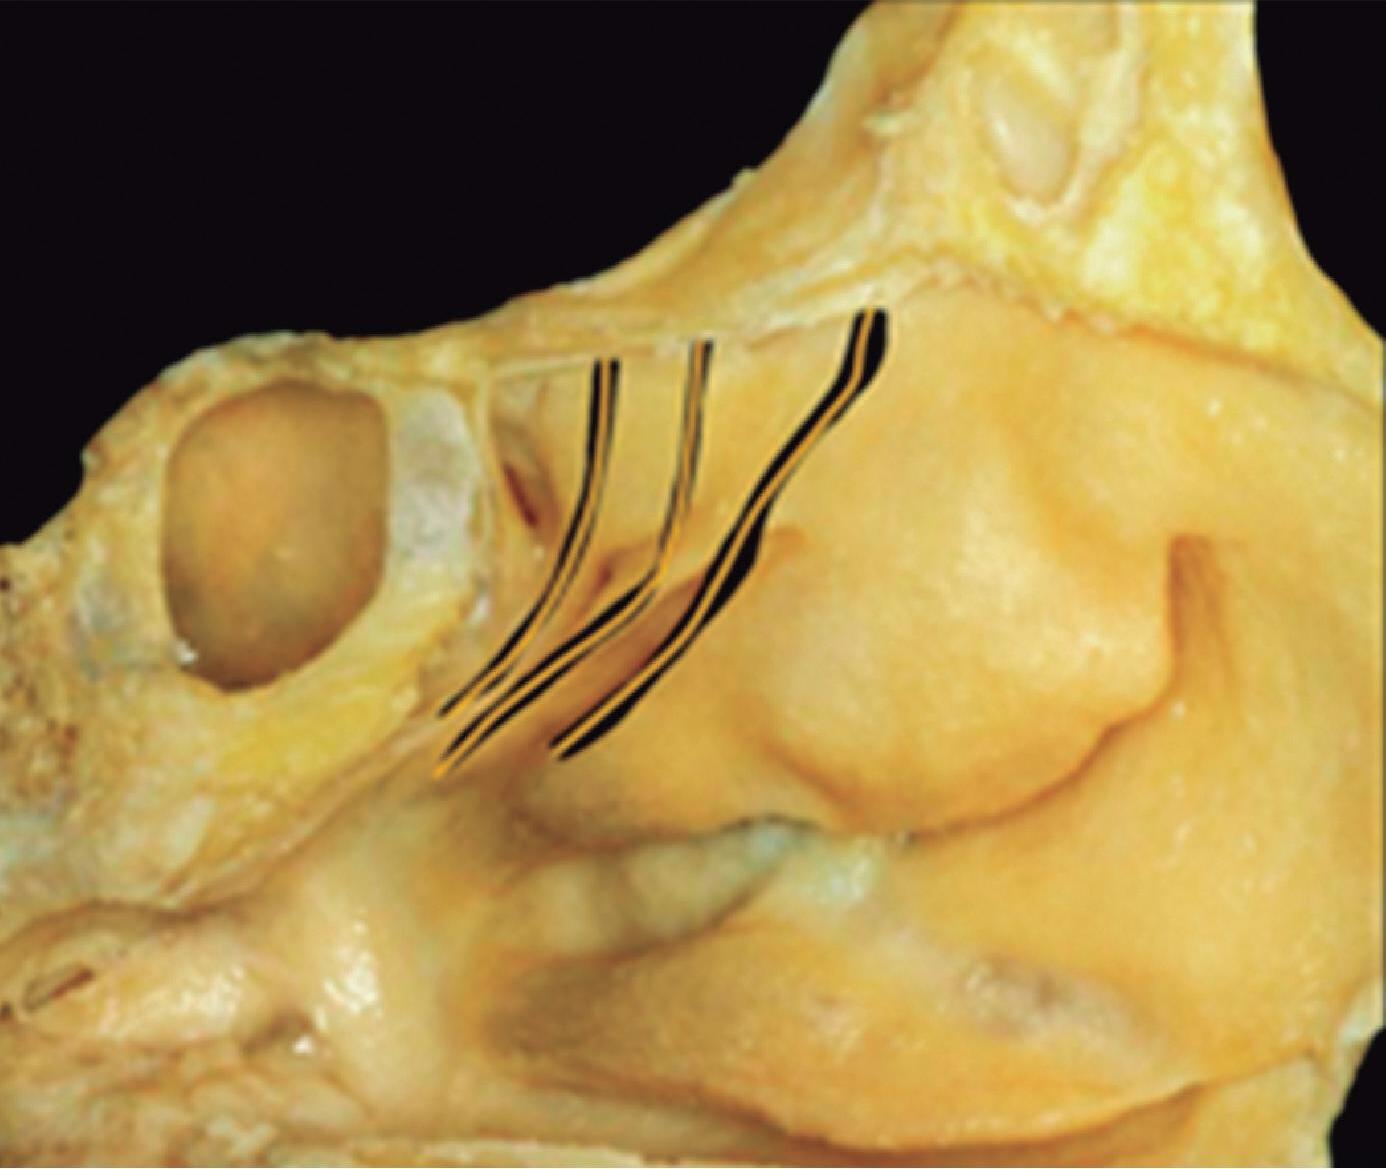

1-13. Montagem em aspecto endoscópico e peça anatômica (Bagatella) demonstrando a relação do processo uncinado e bulha etmoidal com a parede medial da órbita: (1) porção meatal da concha média; (2) processo uncinado; (3) bulha etmoidal; (4) parede medial da órbita.

O meato médio, por servir fisiologicamente aos seios frontal e maxilar, é o mais complexo e o comportamento anatômico do processo uncinado e da bulha etmoidal é arquitetonicamente combinado para exercer função predeterminada. Ambas as estruturas, embora com formatos distintos, ancoram-se ou estão acopladas à parede medial da órbita.